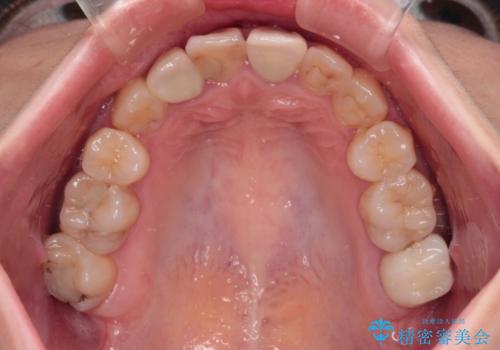

- 奥歯が痛いとのことで来院された患者様です。

上顎親知らず周辺の炎症と、神経組織の失活した歯の炎症による痛みが認められたため、親知らずの抜歯と根管治療を行いました。

根管治療を行った歯はクラウンによる補綴治療が必要となりますが、高校生の頃に行った矯正治療の後戻りも気になるとのことで、補綴治療を行う前に矯正治療を行うこととしました。

後戻りは軽度であり、インビザラインにて歯列を整え、その後にオールセラミッククラウンにて補綴治療を行うこととしました。